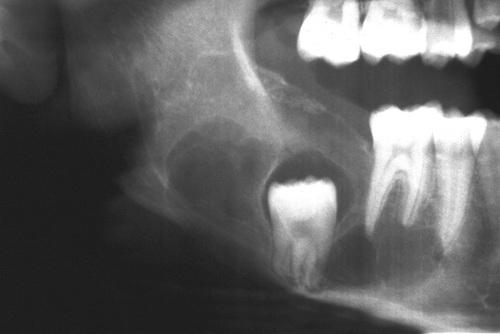

This large, multilocular cyst involves most of the ascending ramus and is growing in an anteroposterior direction.

odontogenic keratocyst (OKC)